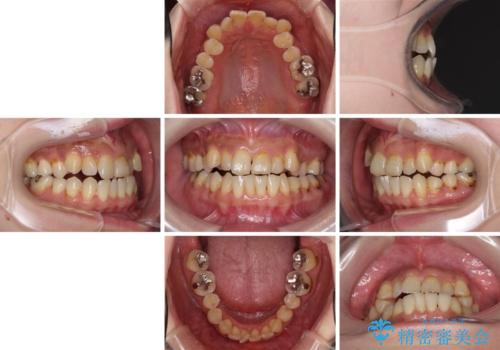

- 歯列不正と、どこで咬んで良いのか分からない咬み合わせを気にして来院された患者様です。

下顎骨は左側にシフトしており、咬み合ったときには奥歯と前歯の一部しか接触していない状態でした。

骨格的な左右差は歯列矯正は改善できないため、上下歯列が全体的に接触することをゴールとしてインビザラインにて矯正治療を行うこととしました。